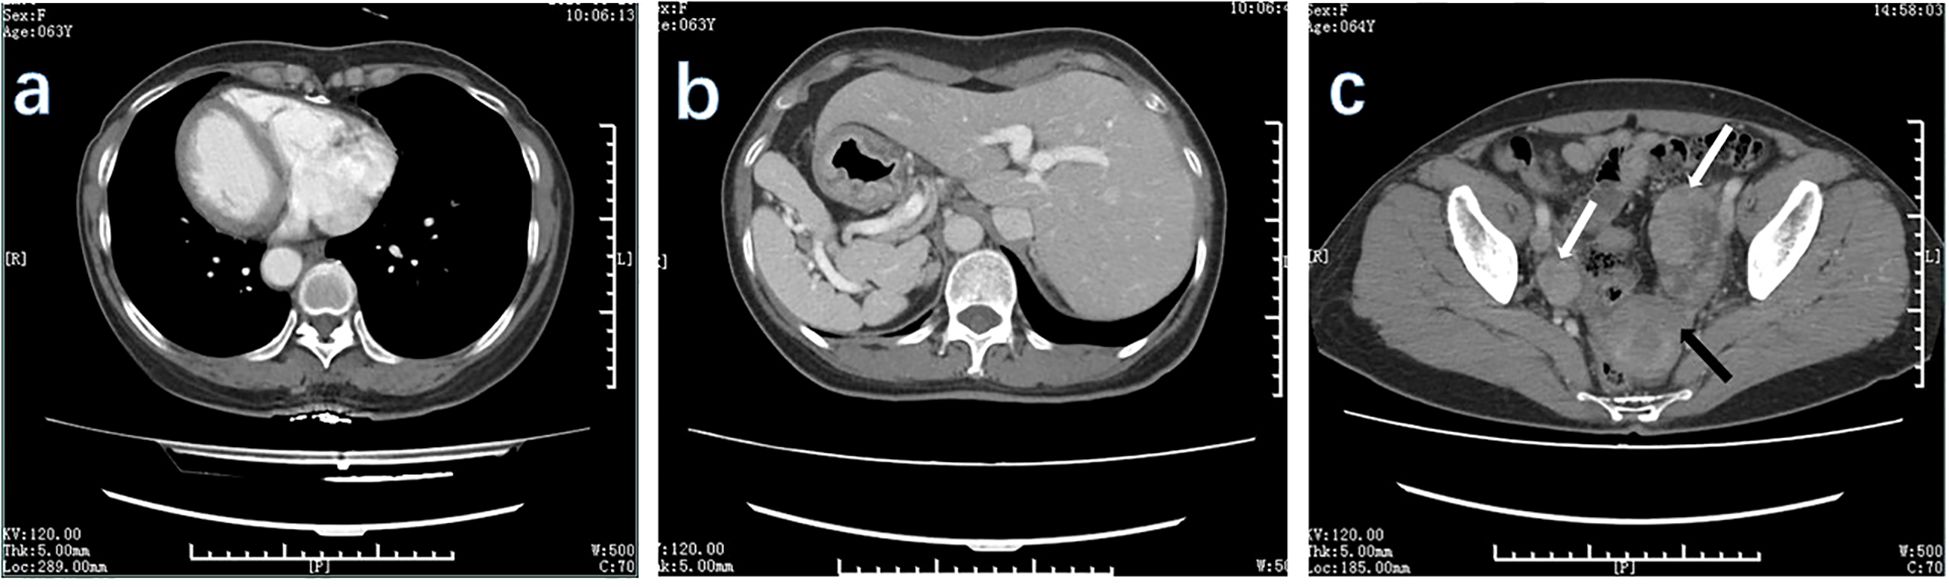

The primary modes of metastasis of gastric cancer are through the bloodstream and lymph nodes. However, in cases such as the Krukenberg tumor (KT), gastric cancer cells can spread to organs within the abdominal cavity and develop implantation metastases. This report describes the treatment process for a patient with situs inversus totalis (SIT), gastric cancer, and a KT. A 63-year-old woman with SIT presented with abnormal vaginal bleeding and was diagnosed with gastric cancer with KT. After careful evaluation, the patient underwent total gastrectomy (Roux-en-Y esophagojejunostomy, antecolic, and D2 lymph node dissection), total hysterectomy plus double adnexectomy, and appendectomy. Considering the patient's SIT, we devised a modified surgical strategy. The surgery was successful. Postoperative adjuvant chemotherapy was administered, and her current evaluation indicated stable disease. Although gastric cancer complicated by KT is rare, it occurs in some cases. Surgical treatment should be considered if both the primary and secondary lesions can be radically resected and supplemented with systemic chemotherapy. For patients with SIT, the surgical approach should be appropriately adjusted with careful preoperative evaluation to ensure procedural safety.